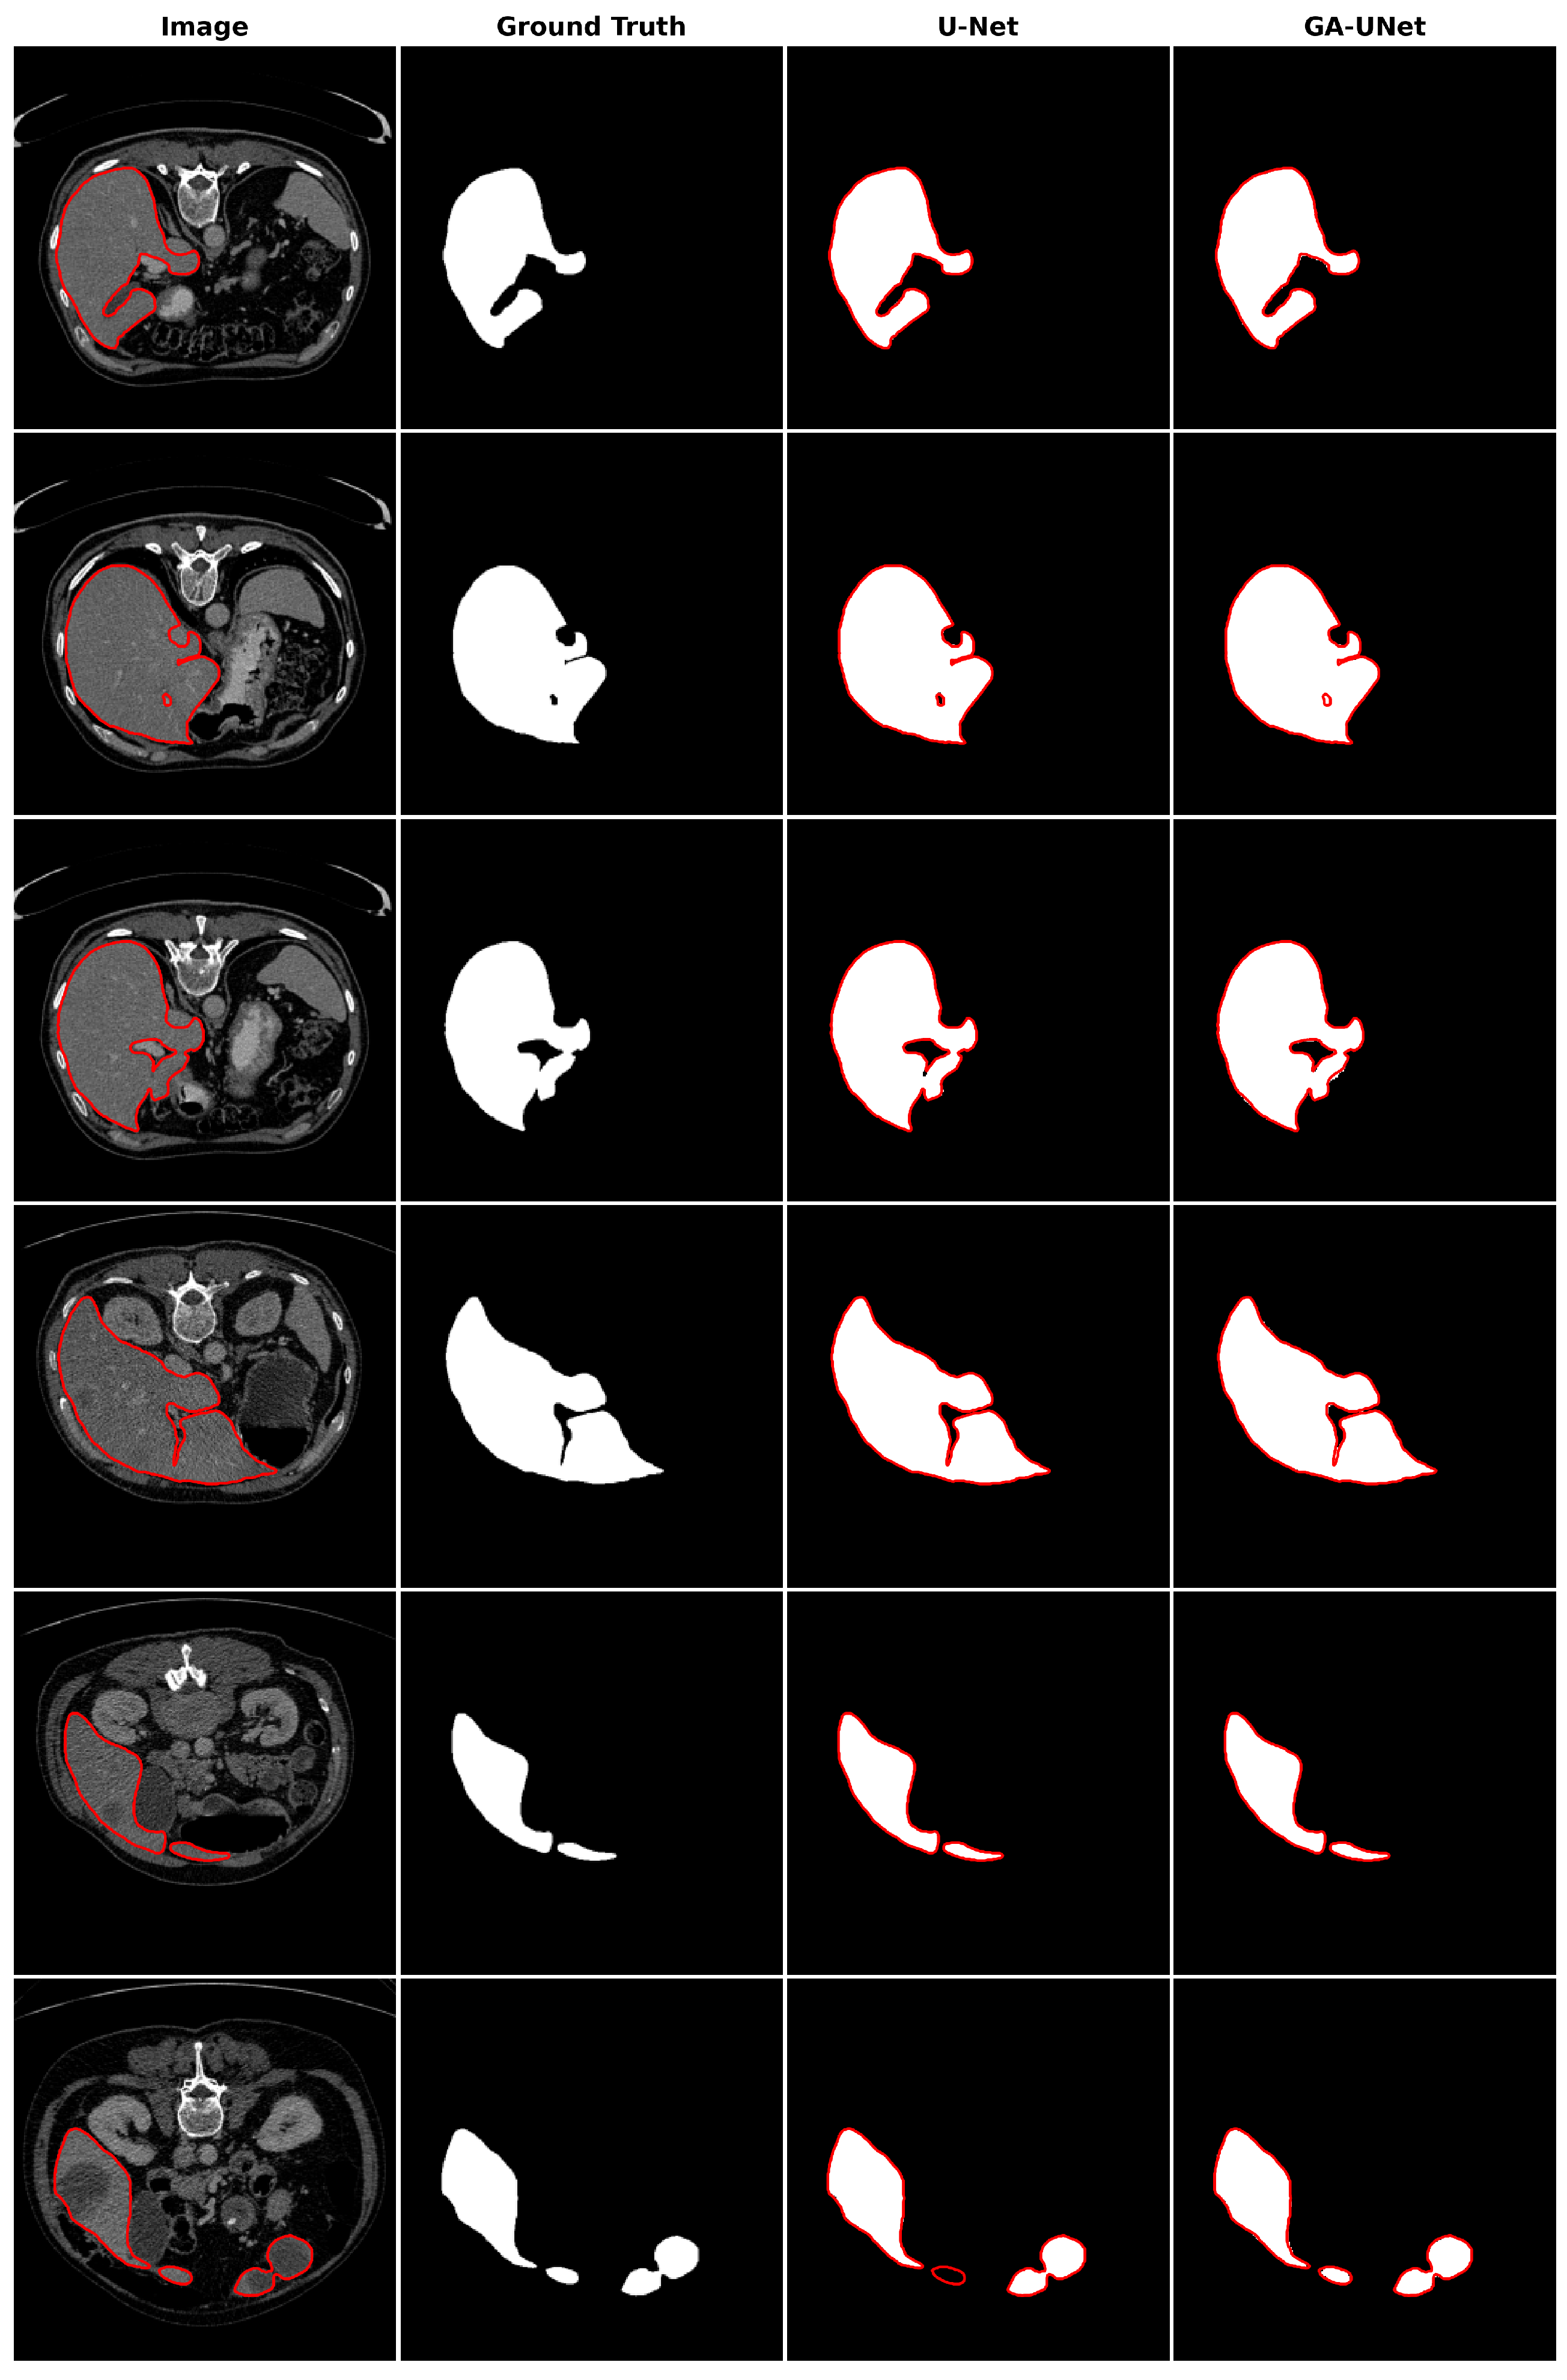

For the qualitative analysis, we show some precise and promising segmentation results in Figure 8 to visually compare our method with the original U-Net [12] model. The lung segmentation result depicted in Figure 8 is deemed satisfactory, as the proposed approach GA-UNet was able to almost completely segment the lung from the CT scan images. But in some instances, as shown in rows 2 and 4, it missed a small portion of the lung.

Figure 8.

Segmentation results on lung segmentation dataset. From left to right, the columns represent in order: the input image, ground truth, U-Net prediction, and GA-UNet prediction. The red curves represents the actual area of the lung.